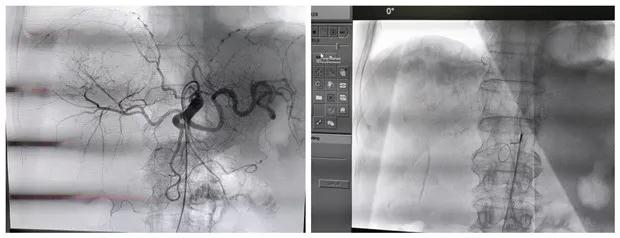

明确诊断后,经科室讨论考虑,患者为肿瘤晚期,失去外科手术机会,经肝动脉及肾动脉栓塞化疗是目前治疗不能手术切除肿瘤的最好治疗方法。经与患方充分沟通后,给予行肝动脉及右肾动脉栓塞化疗术,手术顺利,术后患者恢复良好。

经动脉栓塞是阻断肿瘤的供血动脉,切断肿瘤细胞的营养供应,达到饿死肿瘤细胞的目的;同时给予肿瘤供血动脉灌注化疗,化疗药物浓度高,是常规静脉化疗药物浓度的1000倍,可有效杀死肿瘤细胞。